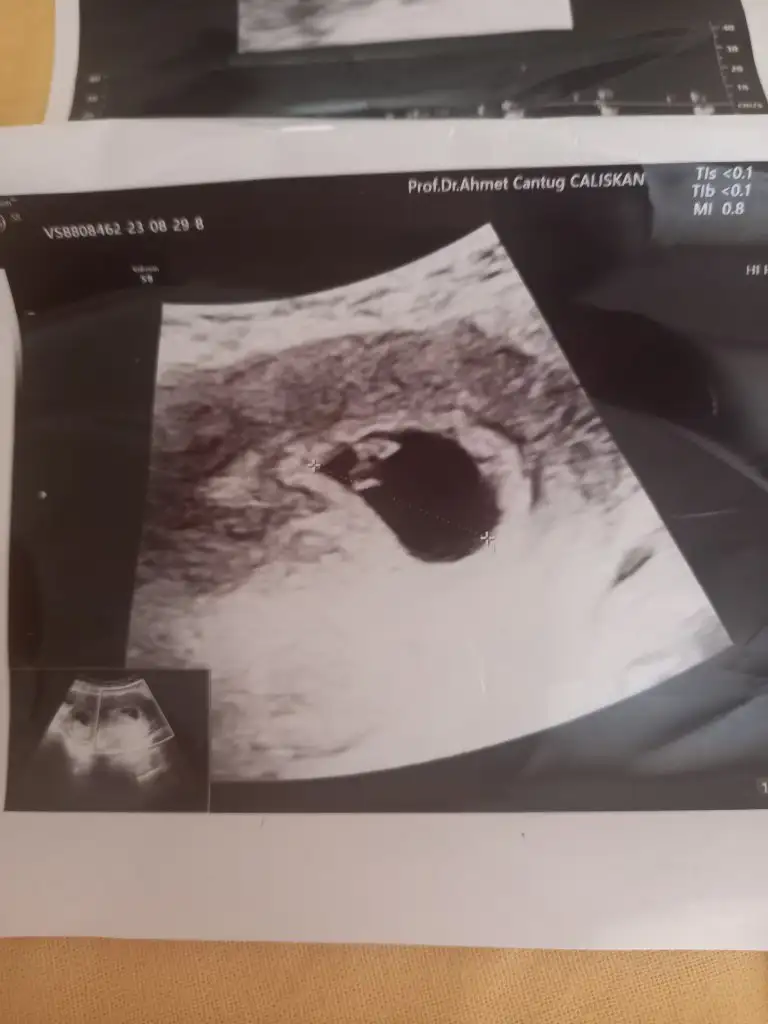

Merhaba benimkinede bakar misiniz 9 haftalık7-8 haftaşık ultrason resmi varsa iyi tahmin yaparım![]()

Nerden anladınız

Daha hiçbir şeyi oluşmamış, el ayak kafa kol vs. Benim 9 haftada her şeyi belirgindiNerden anladınız

O zman sizinki erkekti daha çabuk oluşum gösterirler.Daha hiçbir şeyi oluşmamış, el ayak kafa kol vs. Benim 9 haftada her şeyi belirgindi![]()

Aynen canım benim erkek, erkekler daha çabuk oluşuyor. Tabi istisnalar da var, ama yine de kız diyorumO zman sizinki erkekti daha çabuk oluşum gösterirler.![]()